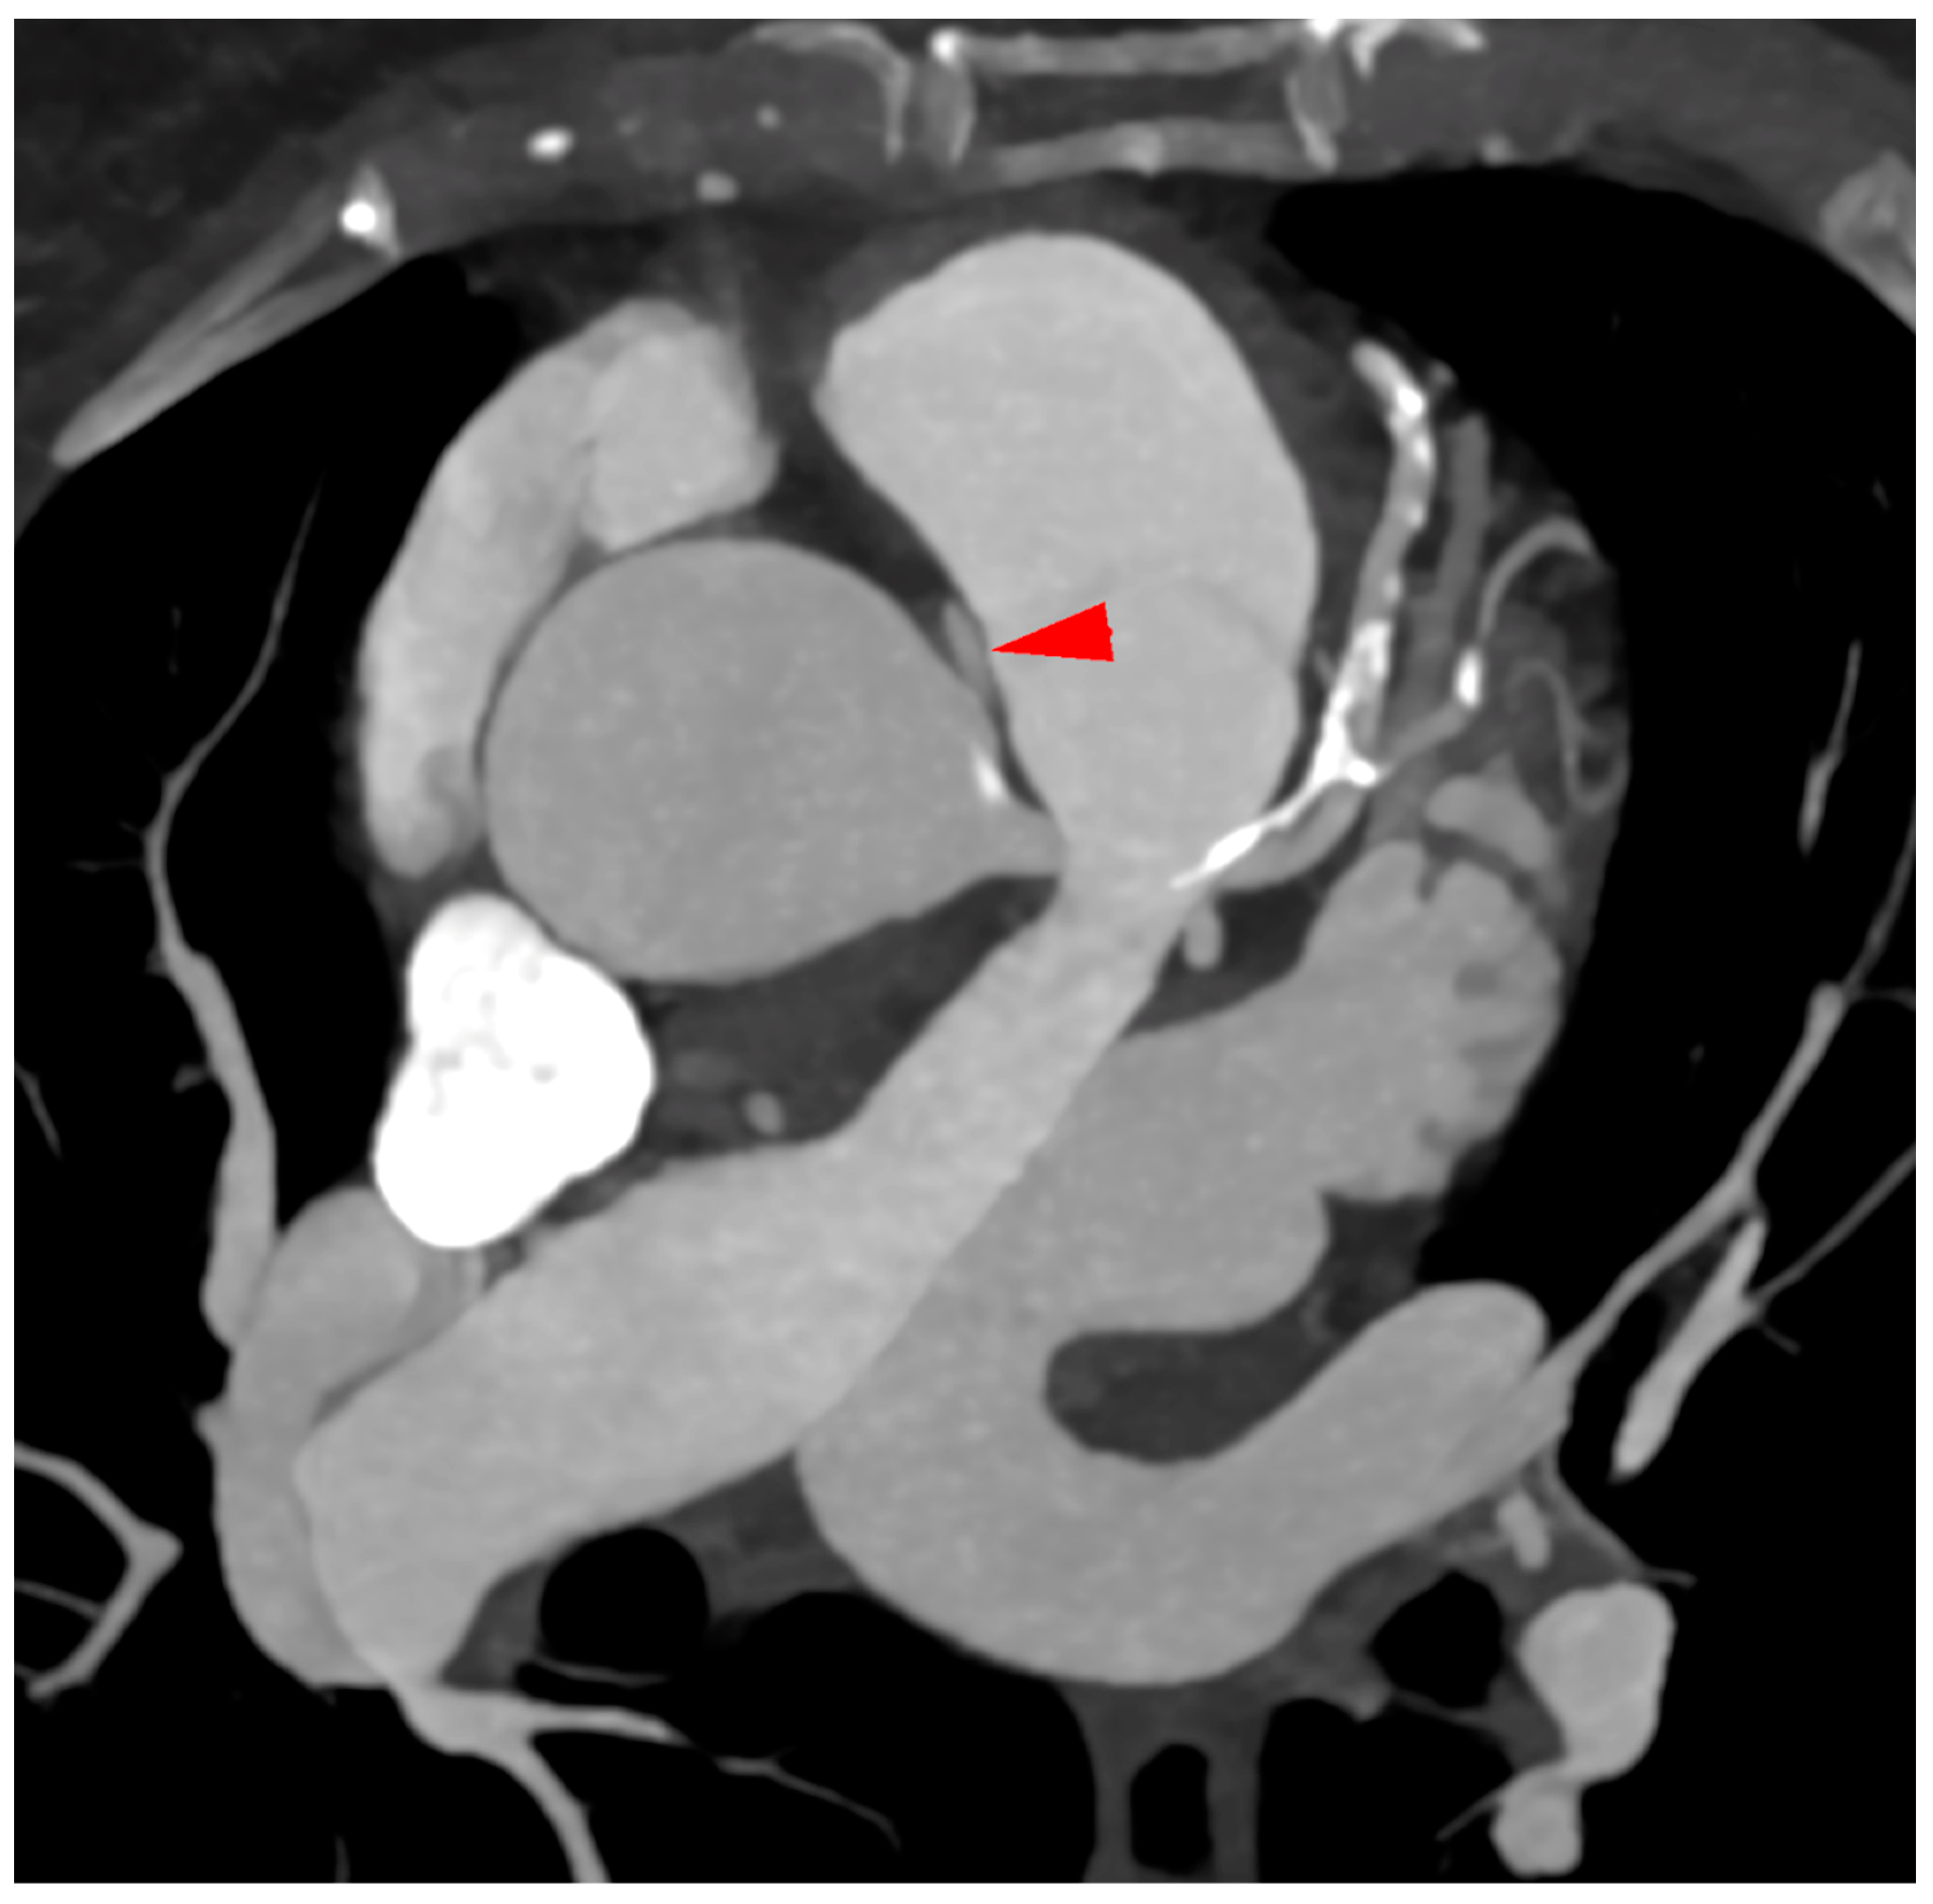

- Incidental vascular finding No. 3: Ectopic Right Coronary Artery Ostium.